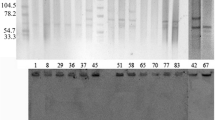

DNA fingerprint profiling of the 65 isolates identified four major clusters (Figure 1), with strains grouped in each cluster sharing high levels of similarity (80-100%).

PFGE identified four major clusters: cluster one grouped 32% of the samples (n=21) with 54.5% similarity. Five of the eleven (45%) plasmid-borne SHV were identified in this cluster, and their mrp were indistinguishable. Remarkably, one isolate (01–007967) did not carry any of the genes, displayed identical MRP to two isolates (01–007961, and 01–008884) carrying both TEM and SHV. Cluster two grouped the majority 41.5% of the isolates (n= 27), sharing 75.6% similarity and forming a broad cluster. Two plasmid-borne SHV and another two CTX-m carrying isolates were identified in this cluster and located distantly from each other. The third cluster is composed of 19% of the samples (n=12), members of this cluster did not share identical MRP pattern. The fourth cluster represented the fewer number of samples 8% (n=5) where one isolate (03–021322) carried the three genetic markers for resistance.

PFGE analysis of the seven K. pneumoniae strains producing CTX-m-15 (Figure 2), using complete linkage, dice band-based similarity coefficient and 1.5% position tolerance, revealed 5 clusters: one pair of isolates (pattern 1) was collected from nosocomial infections at a hospital in Cairo in 2001 (01–015469 and 01–015470; >85% similarity). Another pair (pattern 4) were isolated in Kafr El Shiek governorate from community-acquired infections in 2003 (03–021318 and 03–021320, > 80% similarity) displayed a MRP (pattern 3) that is distantly related to another isolate detected at the same hospital (03–021322, 61.9% similarity). Two isolates each with unique pattern; one was isolated from Mansoura governorate (nosocomial, 02–005285) formed pattern 4), and another isolate from Alexandria governorate (community, 03–018785) formed pattern 5. Five distinct DNA fingerprint patterns were detected with the positive plasmid SHV isolates (Figure 2b). Interestingly, pattern 1, composed of five isolates (01–007951, 01–008666, 01–013906, 01–007724, 01–016401), all were isolated from nosocomial infection collected from Cairo University. The unique MRP patterns 2 and 4, displayed by isolates 03–018785, and 03–021322, respectively, were collected from Kafr El-Shiek General Hospital but was not seen in the seven nosocomial isolates received from the same location (03–002582). Distinct patterns 3 and 5 came from community isolates collected at Zagazig University.

PFGE Analysis. 2a. PFGE analysis of the seven CTXM-15 K. pneumoniae producers strains. The dendrogram was constructed with dice coefficient, complete linkage, and 1.5% position tolerance. The degree of relatedness between K. pneumoniae isolates and those from GenBank is shown on the branches. 2b. PFGE analysis of the 11 K. pneumoniae strains producing SHV-12, SHV5 and SHV-2a. The dendrogram was constructed with dice coefficient, complete linkage, and 1.5% position tolerance. The degree of relatedness among K. pneumoniae isolates and those from GenBank is shown on the branches.